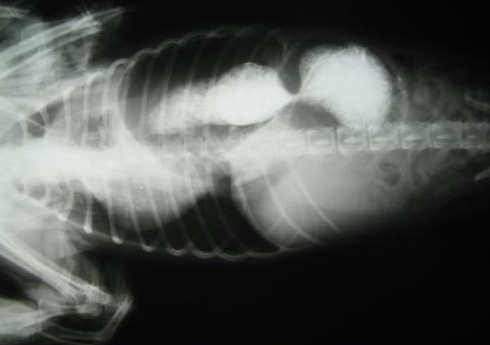

4.胃肠绞窄、坏死 胃、小肠、结肠嵌顿发生血运障碍时,可发生绞窄、坏死。临床可有大便潜血或明显黑便,弥漫性腹膜炎和中毒性休克表现。

6.可能会对心脏,肺组织有压迫。心脏位置发生变化,可能会造成血管扭转。胸腔容量减少,肺组织受压迫,可能会产生呼吸困难